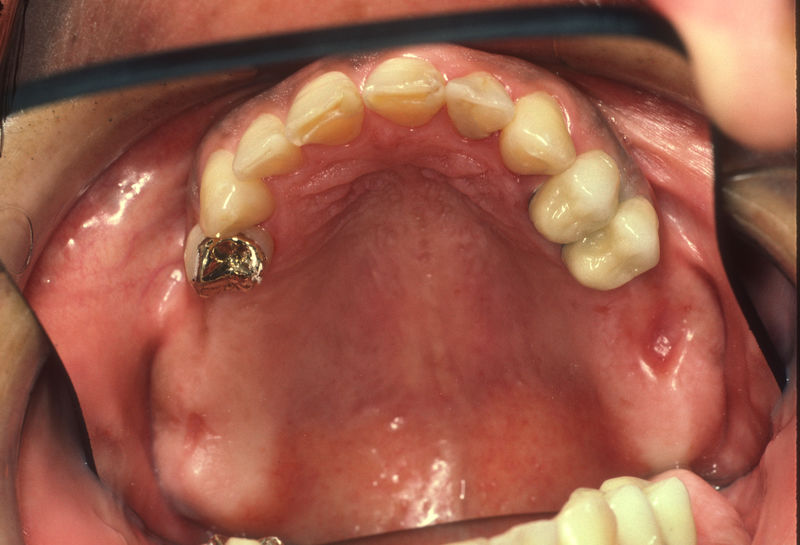

Son estructuras de titanio las cuales se colocan en el hueso y se utilizan para soportar coronas, prótesis fijas, removibles y totales. La colocación de los implantes se hacen previo análisis tomográfico.

Los implantes dentales son pequeños tornillos de titanio u otro material biocompatible que se insertan en el hueso maxilar o mandibular para sustituir la raíz de un diente perdido. Actuando como un soporte sólido sobre el cual el dentista puede colocar un diente artificial (corona), un puente o una prótesis completa.